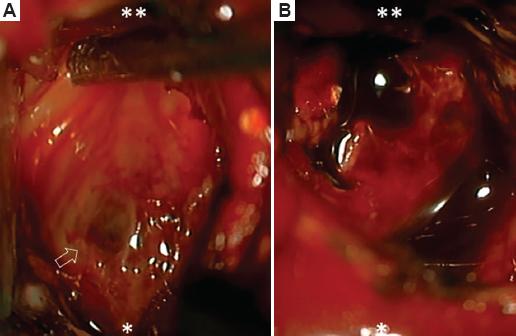

Presentamos el caso de una niña de 10 años que 7 días previos a su ingreso tuvo cefalea y pérdida transitoria del estado de consciencia con posterior recuperación, y desarrolló hemiparesia en el hemicuerpo derecho con fuerza 2/5, ataxia y afección de los nervios craneales izquierdos VI, VII, IX y X. Se le realizó una tomografía de cráneo simple y fue enviada a nuestro hospital para valoración por neurocirugía pediátrica, complementando su abordaje con RM de encéfalo y columna, que evidenció una lesión intraaxial, subpial del tallo cerebral en la unión pontobulbar izquierda, sugestiva de una MC (Fig. 1). Se realizó cirugía a los 10 días de iniciada la sintomatología. Con la paciente en decúbito prono, bajo monitorización neurofisiológica intraoperatoria y con técnicas de microcirugía, se realizó un abordaje telovelar, localizando el piso del ventrículo IV y el colículo facial izquierdo, presentando el colículo un incremento de volumen y un halo de hemosiderina. Se hizo una incisión infracolicular, obteniendo material hemático antiguo, y se identificó una MC de 7 mm que fue resecada totalmente, se corroboró la hemostasia y se cerró por planos de manera convencional (Fig. 2). La paciente fue extubada a las 72 horas. Al persistir con dificultades para la deglución, requirió una gastrostomía endoscópica. Fue egresada a su domicilio a los 7 días del posoperatorio. Se le dio seguimiento en la consulta externa, confirmando el diagnóstico de MC por histopatología. A los 4 meses logra deambular de forma independiente, con una fuerza 4/5 en el hemicuerpo derecho, resolución de la parálisis facial y capacidad de deglución, y se le retira la gastrostomía por lograr un adecuado peso para su talla y edad; aún persistía afección del VI nervio craneal izquierdo. Al año de la cirugía recupera totalmente la fuerza del hemicuerpo derecho y la función de los nervios craneales. Se realiza una RM de encéfalo de control que evidencia la ausencia de la MC (Fig. 3). La paciente no tiene antecedentes de exposición a radiación ni historia familiar de MC, y se descartó una alteración genética.

Figura 2 Fotografía intraoperatoria del piso del ventrículo IV, con la paciente en decúbito prono. A: colículo facial izquierdo incrementado de volumen (flecha). B: salida de material hemático antiguo posterior a la incisión infracolicular. Con dos asteriscos se indica la posición superior y con un asterisco la posición inferior.